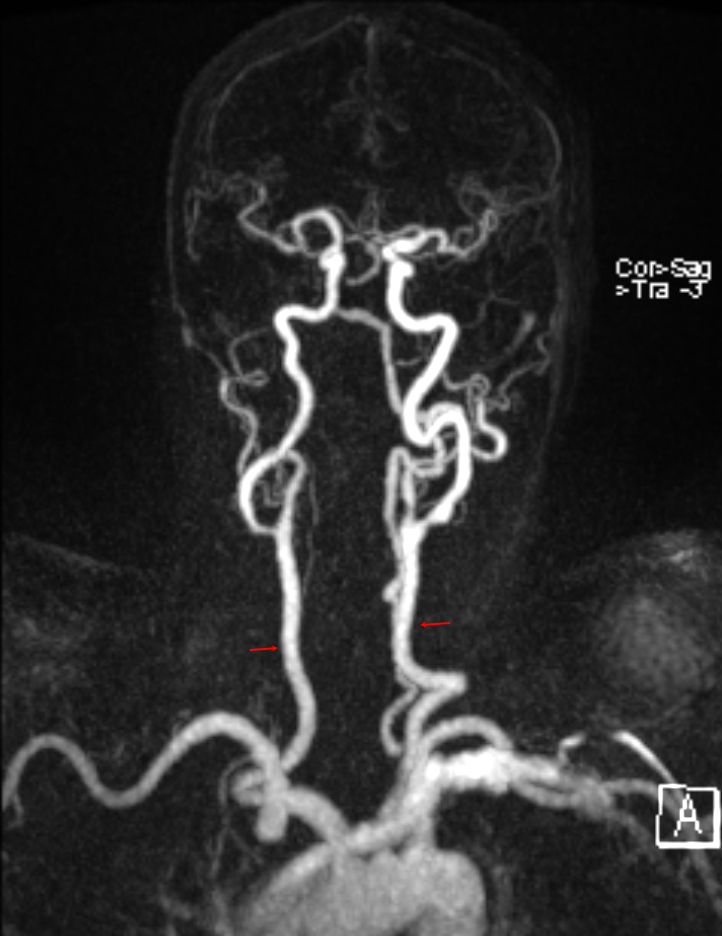

Darstellung der Arteria carotis communis auf beiden Seiten (roter Pfeil) in einer MRI TWIST Sequenz.

Arteria carotis communis im MRI